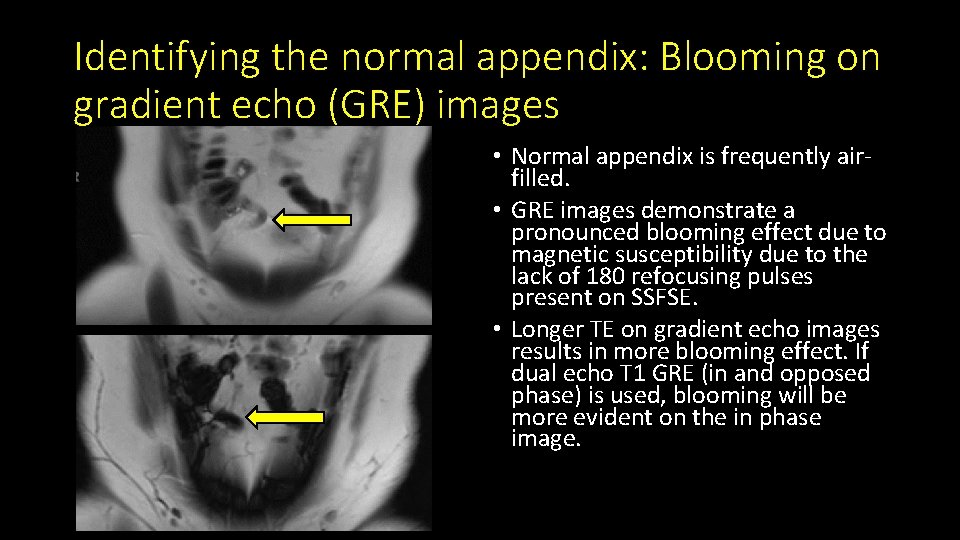

Identifying the normal appendix: Blooming on gradient echo (GRE) images • Normal appendix is frequently airfilled. • GRE images demonstrate a pronounced blooming effect due to magnetic susceptibility due to the lack of 180 refocusing pulses present on SSFSE. • Longer TE on gradient echo images results in more blooming effect. If dual echo T 1 GRE (in and opposed phase) is used, blooming will be more evident on the in phase image.